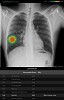

قدمت "جنرال إلكتريك للرعاية الصحية" اليوم "منظومة العناية الصدرية"، وهي مجموعة برمجية من ثماني خوارزميات للذكاء الاصطناعي قائمة على حلول "لونيت إنسايت" لتصوير الصدر ...